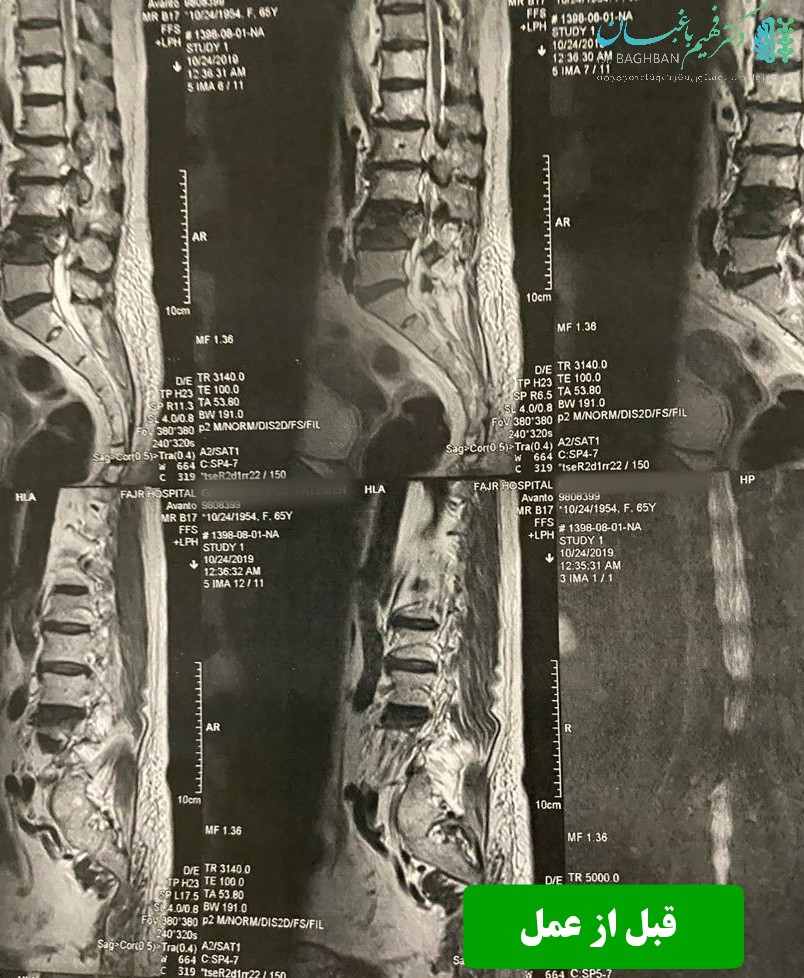

خانم ۸۴ ساله که با درد شدید کمر و ناتوانی در راه رفتن و سوزش و کرختی پاها مراجعه کردند. بیمار دچار شکستگی مهره L4 شده بود که سبب تنگی شدید کانال شده بود. بیمار تحت عمل جراحی جهت کاهش فشار از ریشه های عصبی و تزریق سیمان جهت بازسازی و استحکام مهره L4 قرار گرفت.

قبل از عمل

قبل از جراحی